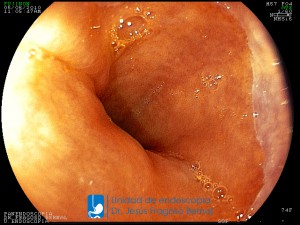

La Unidad de Endoscopía fue creada en 2002 por el Dr. Jesús Fragoso Bernal, es pionera en el estado por la utilización de la tecnología más avanzada, que nos permite ofrecer servicios integrales de diagnóstico y tratamiento para las enfermedades del aparato digestivo.

El profesionalismo de nuestro personal, altamente especializado, se distingue por la calidad y calidez de nuestros servicios con el objetivo de brindar una atención de excelencia en el ambiente más confortable para comodidad y seguridad de nuestros pacientes.

"La Unidad de Endoscopía se ha caracterizado por un progreso continuo desde su inicio marcando la pauta en los procedimientos endoscópicos en el estado de Tlaxcala y estando siempre a la vanguardia tecnológica."

Dr. Jesús Fragoso Bernal